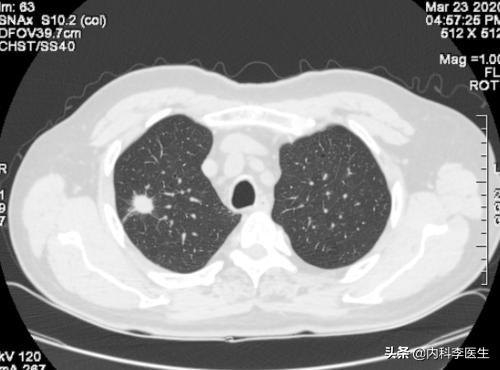

Il existe des nodules pulmonaires multiples et solitaires, et les nodules pulmonaires multiples sont souvent observés à la suite d'une tuberculose ou d'une pneumoconiose, qui sont toutes plus faciles à diagnostiquer avec une anamnèse typique ou une anamnèse du lobe gauche. Les nodules dont nous parlons généralement sont des nodules pulmonaires isolés.

Les examens médicaux étant de plus en plus fréquents, les nodules pulmonaires sont de plus en plus souvent détectés. Les nodules pulmonaires sont un terme d'imagerie, et la définition d'imagerie d'un nodule pulmonaire est une petite lésion bien définie qui est complètement entourée par le parenchyme pulmonaire (Diamètre ≤30mm). La morphologie des nodules est classée comme solide ou sub-solide ; les nodules sub-solides sont eux-mêmes classés en nodules de verre dépoli et en nodules partiellement solides. Les lésions de plus de 30 mm de diamètre sont des masses plutôt que des nodules et ont une probabilité plus élevée d'être malignes.

Environ 99 % des nodules pulmonaires sont des lésions bénignes.Les causes les plus fréquentes sont les granulomes infectieux et les tumeurs bénignes (par exemple, les tumeurs malignes pulmonaires), et parfois les lésions vasculaires et inflammatoires.Environ 1 % des nodules pulmonaires sont malins.Les causes courantes des nodules pulmonaires malins sont le cancer primitif du poumon, les métastases pulmonaires et les tumeurs carcinoïdes.